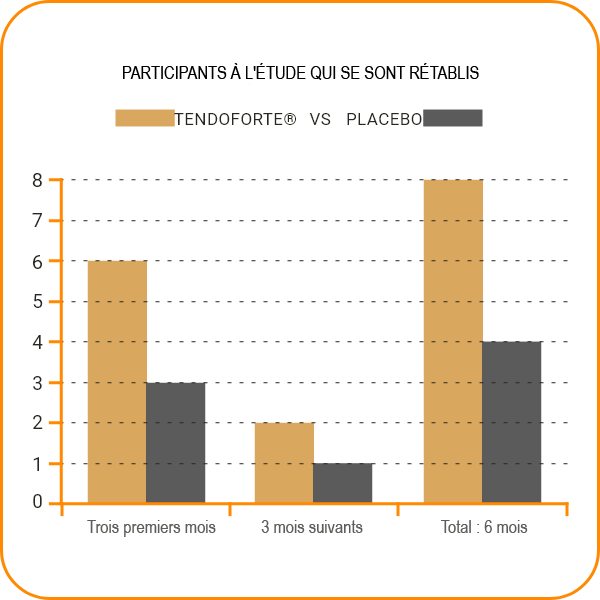

L'étude a porté sur 18 coureurs, hommes et femmes, incapables de s'entraîner en raison de douleurs au tendon d'Achille. Les participants ont reçu soit un placebo, soit TENDOFORTE® en association avec des exercices de renforcement musculaire du mollet effectués deux fois par jour pendant six mois, selon une approche croisée.

Le groupe AB a reçu TENDOFORTE® pendant les trois premiers mois avant de passer au placebo, tandis que le groupe BA a d'abord reçu un placebo avant de passer à TENDOFORTE®.

Avec l'aide de TENDOFORTE®, 12 des 18 participants à l'étude ont repris la course à pied en seulement trois mois. La supplémentation a amélioré la stabilité et la fonction du tendon d'Achille, tout en réduisant la douleur.